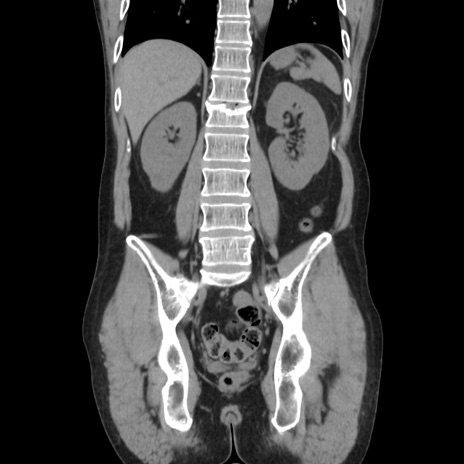

症例37(冠状断像)

【症例】40歳代 男性

【主訴】腹痛

【現病歴】4時間ほど前に電車に乗車中に臍部上より腹痛出現。徐々に増悪し起立困難となり、救急外来受診。生ものは数日食べていない。今朝お雑煮を食べた。

【身体所見】BT 36.8℃、BP 117/84mmHg、HR 91/min、SpO2 97%、苦悶様、腹部:臍上部広範囲圧痛あり、反跳痛±

【データ】WBC 8100、CRP 0.03